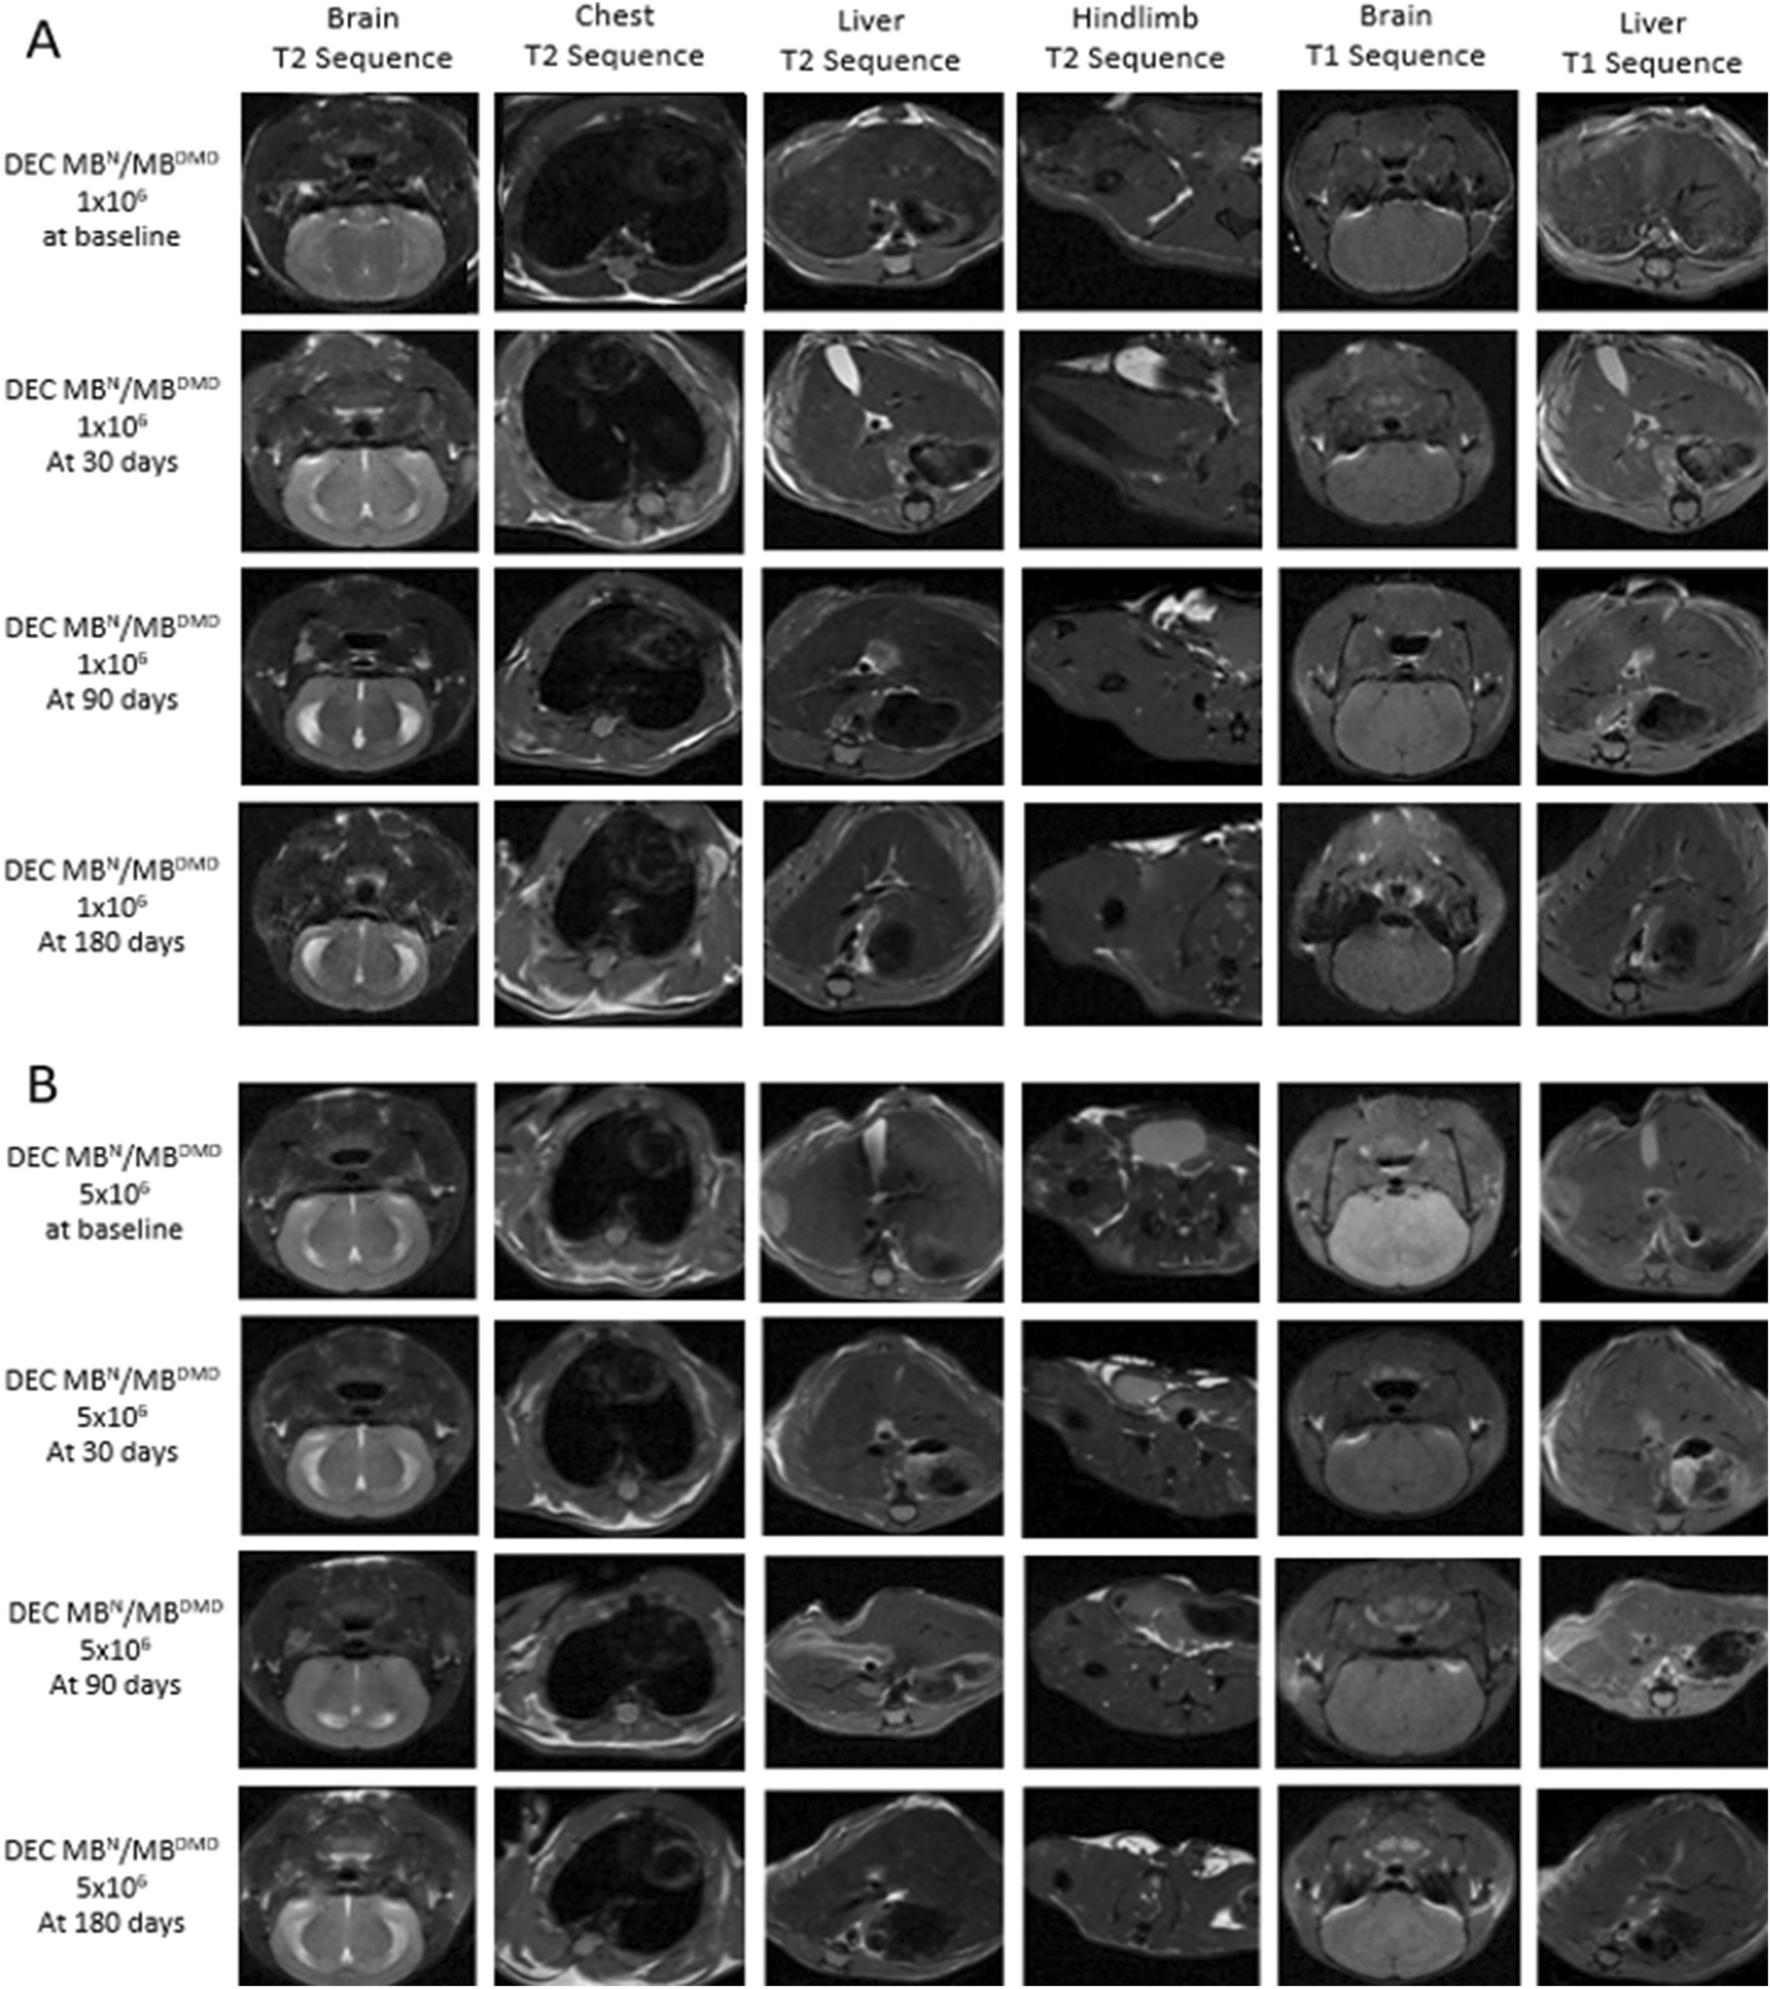

Human DEC Therapy Safety was Confirmed by Magnetic Resonance Scanning and Autopsy Assessment, Revealing Lack of Tumor Formation up to 180 days After Systemic-Intraosseous Administration of Human DEC Therapy

Assessment of MRI images performed at 180 days, the study endpoint for both DEC therapy groups: the 1 × 106 dose (Fig. 2A) and 5 × 106 dose (Fig. 2B) and the vehicle-injected control, confirmed lack of tumor formation in the T2 weighted images acquired for each section of brain, chest and abdominal wall. Moreover, lack of tumor formation was confirmed on T1 weighted images acquired for brain and liver since greater soft-tissue resolution facilitates tumor detection in solid organs. These images acquired at 180 days study endpoint were comparable with the images taken before DEC administration and during the 30 and 90 day follow-up. These findings confirm lack of tumorigenicity and DEC therapy safety at long-term follow-up.

Magnetic Resonance Imaging (MRI) confirms the lack of tumor formation and safety of human Dystrophin Expressing Chimeric (DEC) Therapy assessed up to 180 days after intraosseous administration of two doses (1 × 106 and 5 × 106) of DEC Therapy. Safety assessment of DEC therapy by comparative analysis of MRI images at time 0 before DEC injection and at 30, 90, and 180 days after intraosseous administration of A. 1 × 106 DEC and B. 5 × 106 DEC. Evaluation of organs at the highest tumor risk rate (brain, chest, liver) and the right hind-limb (the femoral shaft level of the DEC injected limb) confirmed lack of tumor formation in all tested organs up to day 180 post-DEC administration (31 cm bore size 9.4 Tesla Agilent MRI System) (Model 1025, SA Instruments Inc., Stony Brook, NY, USA). Each mouse was scanned at each time-point at three sections: brain, chest, and pelvis. T2 weighted images were acquired for each section and T1 weighted images were acquired for brain and liver (greater soft-tissue resolution facilitates tumor detection in solid organs). Scan parameters for T2 weighted images: field of view 40 × 40mm2, matrix size 128 × 128, TR = 2000 ms, echo train length 16, effective echo time 28 ms. Scan parameters for T1 weighted images: field of view 40 × 40mm2, matrix size 128 × 128, TR = 550 ms, echo time 28 ms

Since tumorigenicity is considered one of the most challenging aspects of current gene as well as cell-based therapies, we have assessed animals by MRI scanning before and at 30-, 90- and 180 day study endpoint after DEC therapy administration. The T2 weighted images of brain, chest, and pelvis as well as the T1 weighted images for brain and liver, confirmed the lack of tumor formation over the entire long-term follow-up period.